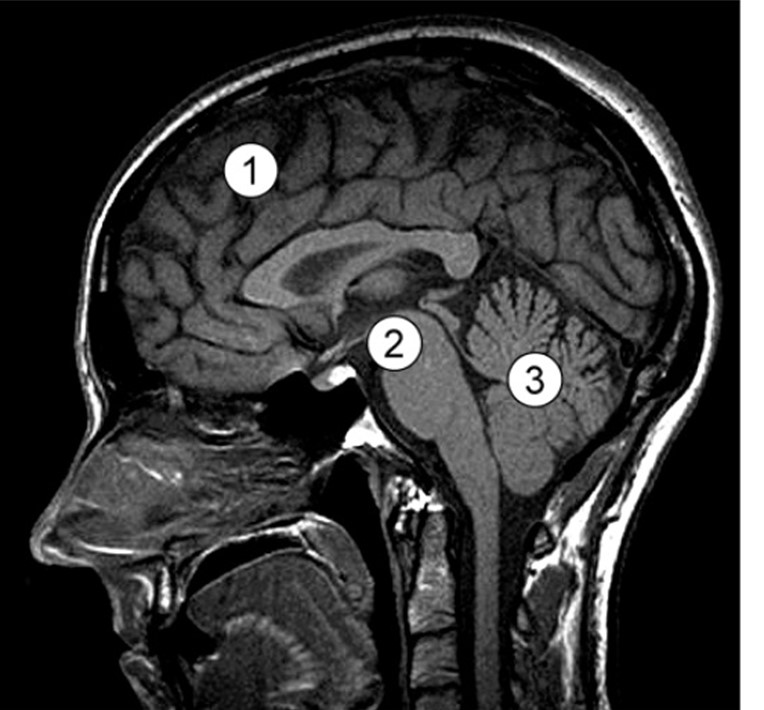

In de onderstaande afbeelding zie je een MRI-scan van de hersenen.

Op de foto zijn 3 verschillende hersendelen gemarkeerd. In welk hersendeel of welke hersendelen bevinden zich vooral autonome centra?